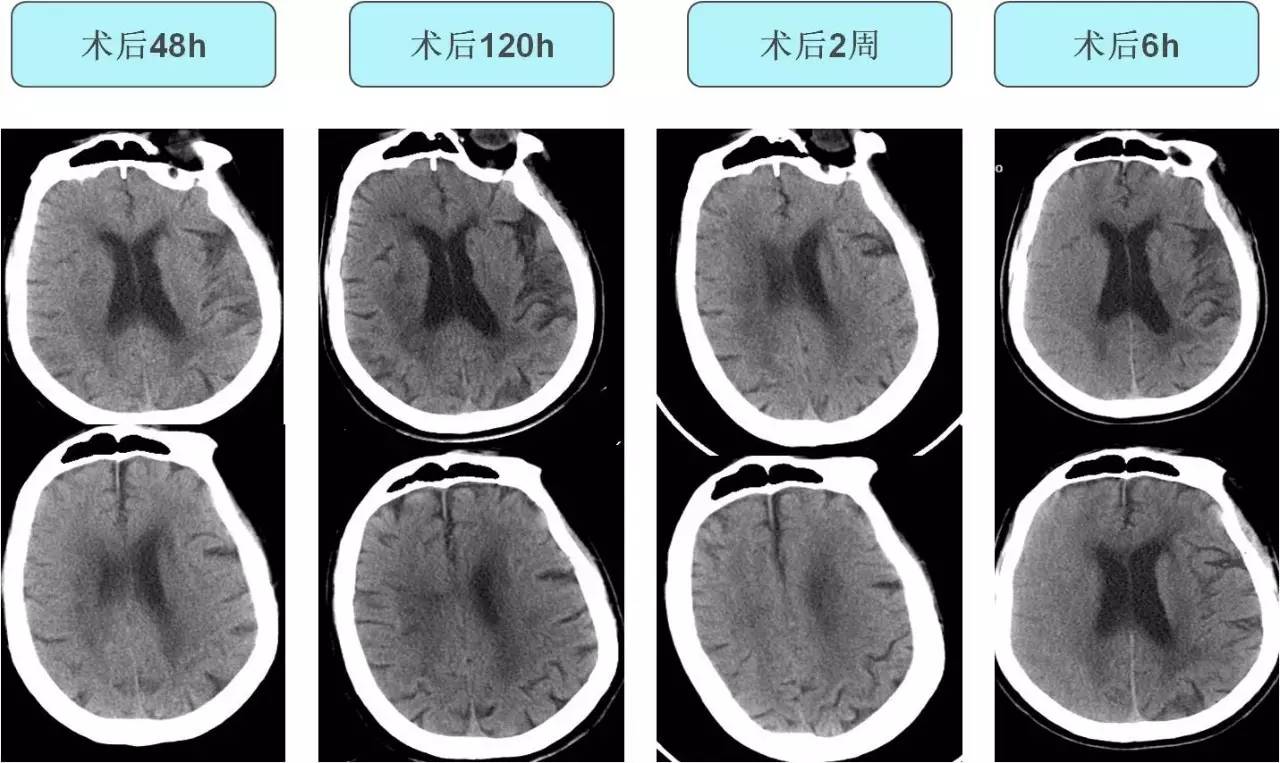

不同时间CT表现

》停用多巴胺,监测血压,加用乌拉地尔泵入,维持收缩压90-120mmHg;

》甘露醇 125ml Q6h,脱水、降颅压;

》依达拉奉 30mg Bid,鲁米那 100mg Bid,抗氧化、脑保护治疗;

》物理降温,地塞米松10mg 入壶,减轻急性应激反应,奥美拉唑保护胃黏膜;

》抗感染治疗;

》继续应用抗血小板聚集药物。